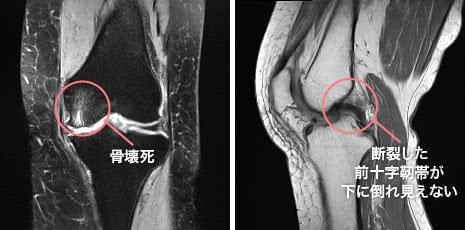

実際の症例2

- 年齢・性別

- 62歳・女性

- お悩み

- 近医で薬物療法を行うも改善なし。来週予定あり早く痛みをとって欲しい。

- 画像所見

- 大腿骨内側顆の骨壊死が、疼痛の原因と考えられる。前十字靭帯は断裂し不明瞭な状態。

- 診断

- 半月板のダメージは少なく、変形も強くないが、骨壊死があるため培養幹細胞治療が有効と考え提案。